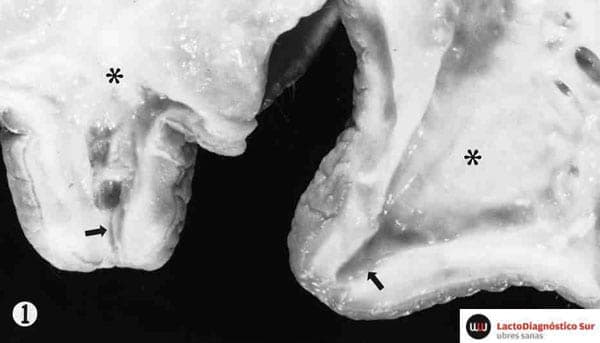

Bovine Teat Atresia Associated with Horn Fly (Haematobia irritans irritans (L.))-induced Dermatitis - J. F. Edwards y Col.- Vet Pathol 2000